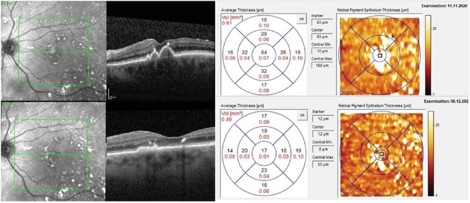

A significant reduction in macular drusen volume, without photoreceptor or retinal pigment epithelium loss, plus a four-letter increase in BCVA, was observed (75 to 79 letters) at month 13 following four PBM treatments. Source: LIGHTSITE III study (Creative Commons 4.0 CCBY-NC-ND)¹